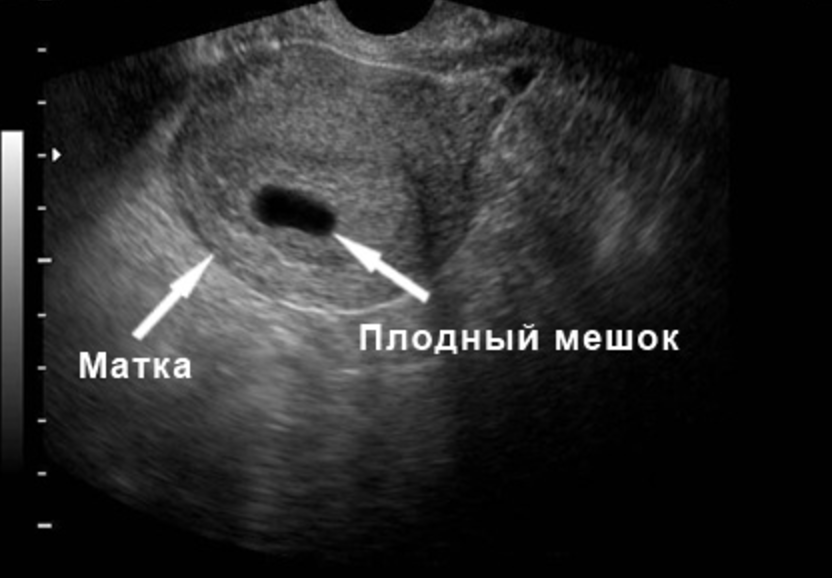

Первым и самым основным признаком нормальной маточной беременности является плодное яйцо в матке. С помощью ультразвукового исследования оно визуализируется через неделю после задержки менструации

На УЗИ проводится измерение диаметра плодного яйца в соответствии с неделями беременности, размеры в мм (например, плодное яйцо 6 мм, плодное яйцо 7 мм). Это помогает наиболее точно установить срок беременности, так и сделать выводы насколько правильно развивается ребенок на ранних сроках.

Для установления наличия и срока беременности врач проводит трансвагинальное УЗИ. Этот доступ позволяет лучше рассмотреть полость матки, достовернее измерить размер и оценить структуру плодного яйца. Помимо визуализации самого плодного яйца врач обязательно оценивает все внутренние органы репродуктивной системы у женщины: матку, шейку, яичники, а также мочевой пузырь. У худых женщин на ранних неделях плодное яйцо иногда бывает видно и с помощью трансабдоминального доступа.

На раннем сроке с 4 по 6 недели срок беременности устанавливают по диаметру плодного яйца. Для этого врач проводит измерение диаметра плодного яйца по его внутреннему контуру в 3 взаимоперпендикулярных плоскостях.

Трансвагинальное УЗИ покажет плодное яйцо в полости матки, когда наступят 4,5 – 5,0 недель беременности. Стоит отметить, что врачи считают продолжительность беременности с первого дня крайних месячных. То есть не стоит сразу же торопиться на УЗИ, если задержка менструаций составляет 1 – 2 дня. Эхография может показать первые признаки гестации только спустя 3 – 5 суток задержки от даты ожидаемых месячных.